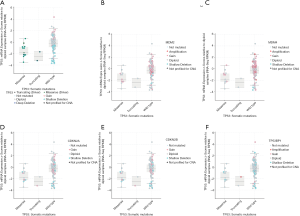

Different mutation types may have distinct biological functions in various cancers, and the co-expression of genes may also affect gene functions. Using the cBioPortal database, we explored the location and types of mutation, as well as co-expression, among genes related to the TP53 signaling pathway. Among these genes, TP53 (2.3%) was the most frequently aberrant gene in WT, followed by MDM4 (0.8%), and then MDM2 and TP53BP1 (0.2%). The most common types of mutation in TP53 were missense and deep deception, while amplification was the most common mutation in MDM2, MDM4, and TP53BP1 (Figure 3A,B). The three-dimensional structure of TP53 is shown in Figure 3C.

The location of mutations in TP53 are shown in Figure 4. The significant co-expressed genes in the TP53 signaling pathway included ZNF609 (zinc finger protein 609), WRAP53 (WD40-encoding RNA antisense to p53), CNOT2 (CC chemokine receptor 4-negative regulator of transcription 2), ANGEL2, TMEM255A, and CDH13 (cadherin 13) (Figure 5). Further, we investigated the relationships of the mutation types (Figure 6), copy number alterations (CAN, Figure 7), and methylation (Figure 8) with the expression levels of defined genes. The gene expression levels were negatively correlated with methylation, but the CNA and mutated type did not have a significant influence. Figure 9 shows the relationship between the genes in the TP53 signaling pathway.